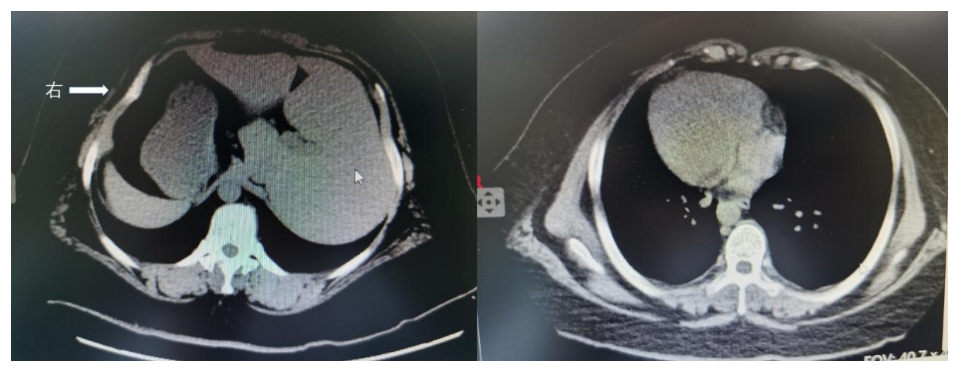

CT图提示患者内脏反转,肝脾位置互换,心脏位于右侧